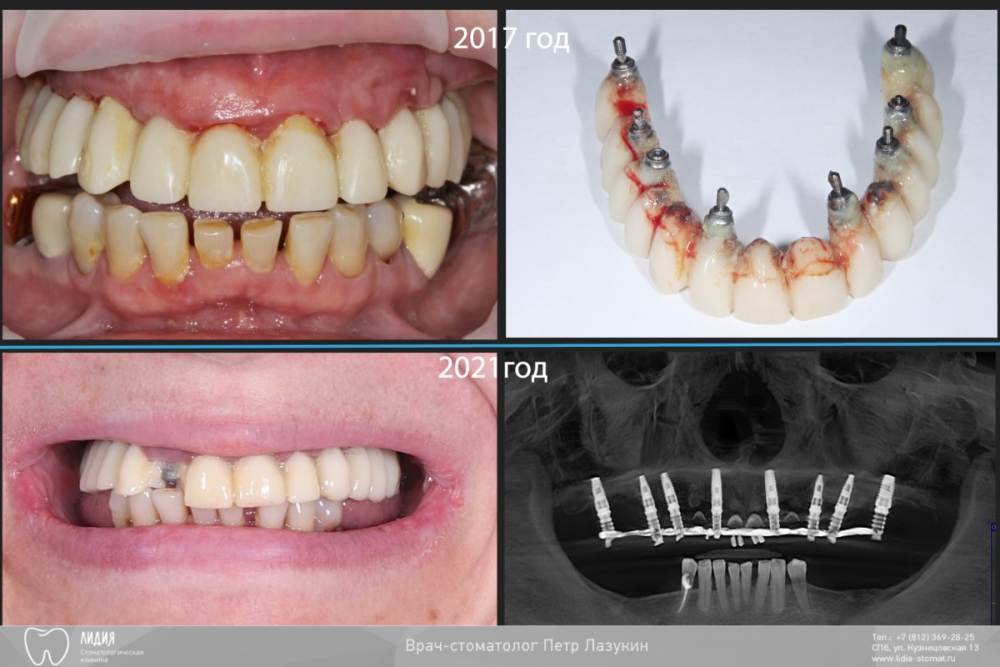

pit Опубликовано 5 октября, 2021 Поделиться Опубликовано 5 октября, 2021 Клинический случай. Старт работ в 2015 году. План простой: Полная дуга, верхняя челюсть. Начали в 2015, закончили в 2021. Какой был план? Зубы в/ч все под удаление. Фронт был временно сохранен для временного протезирования. Установлены импланты с костнопластическими манипуляциями. В качестве временных коронок использованы металлокерамические коронки. Следующим этапом, после интеграции, было открытие имплантов и изготовление временных коронок. И тут пациент пропал на 2 года, а затем еще на четыре)))). Лишь поломка времянок, через 6 лет, сподвигла пациента обратиться за изготовлением постоянных коронок. Протокол и комменты в слайдах. КТ после протезирования. 11.mov 1 2 2 Ссылка на комментарий